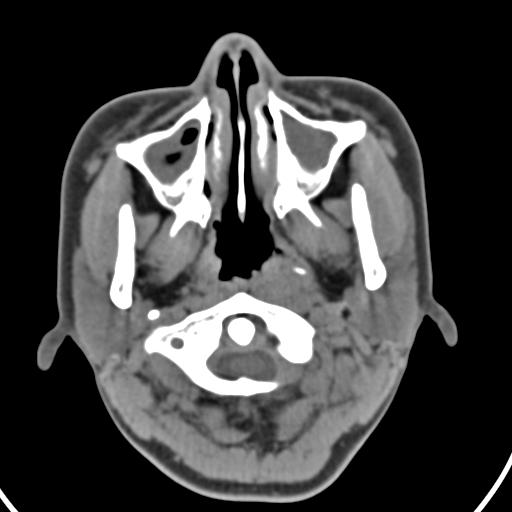

以下是引用zjzjr在2008-12-5 11:46:00的发言:[br]脂肪密度,壁有钙化.考虑口咽部皮样囊肿可能性大.双侧上颌窦炎,双侧下鼻甲粘膜肥厚.增殖腺肥大,扁桃体亦增大,考虑炎性.

以下是引用随光逐影在2008-12-5 18:27:00的发言:[br]1)考虑左侧茎突过长综合征并茎突舌骨韧带囊肿形成突入咽部;左侧咽部慢性炎症。2)鼻咽腺样体肥大。3)双侧扁桃体肿大。4)双侧上颌窦炎。5)双侧下鼻甲粘膜肥厚。